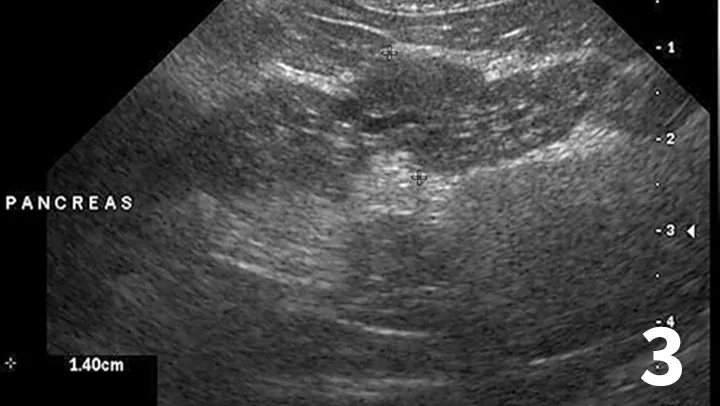

Figure 1

H&E-stained section (20× objective ) of a feline liver with periductal lymphocytic inflammation (arrow) centered around portal areas with concentric rings of fibrosis consistent with lymphocytic cholangitis.

The chronicity of lymphocytic cholangitis is believed to represent a later stage of neutrophilic cholangitis or may represent a separate disease entity. It is characterized by a moderate-to-marked infiltration of the portal areas by small lymphocytes with or without biliary hyperplasia, portal or periductal fibrosis, or bridging fibrosis (Figure 1). The underlying cause is unknown, but 1 possible cause is an immune disorder.<sup11 sup>